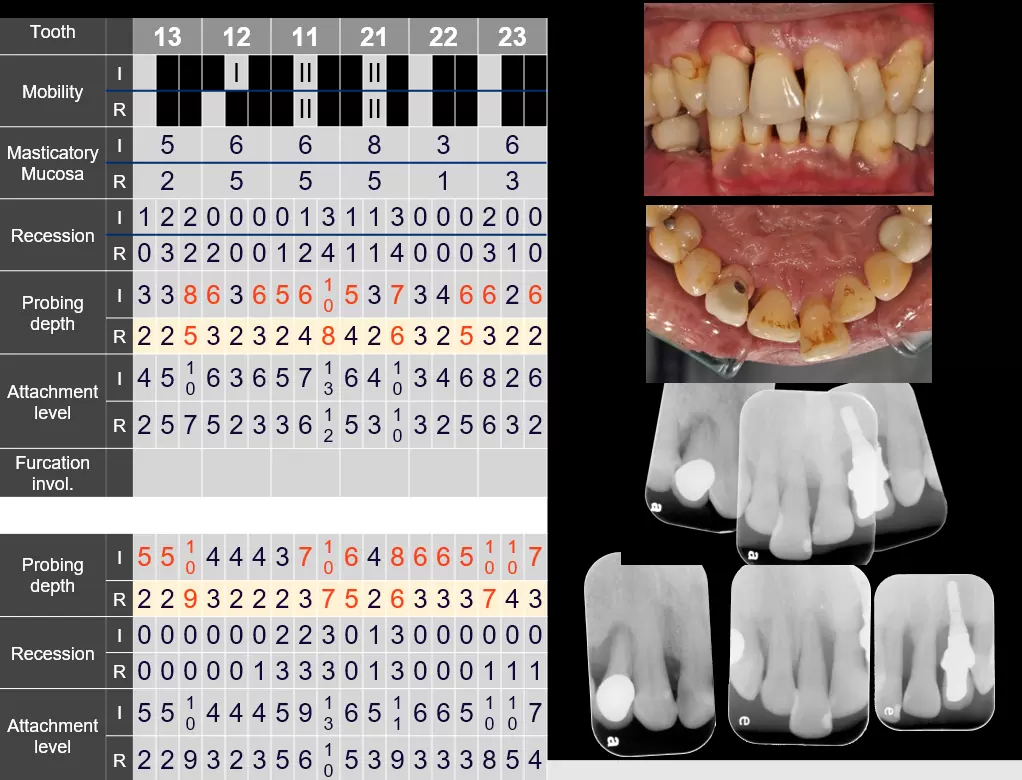

其中,牙周囊袋探測是相當關鍵的步驟,牙醫會用標有刻度的牙周探針,放入牙齒與牙齦的縫隙(牙周囊袋)間測量深度,藉此判別牙周病的嚴重度。